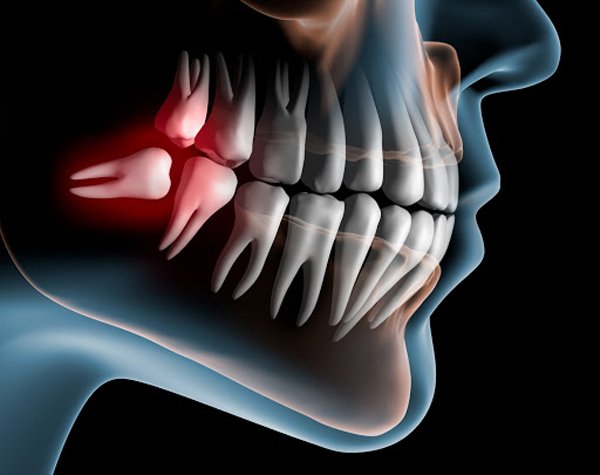

Răng khôn (hay còn gọi là răng số 8, răng cối lớn thứ ba) là chiếc răng mọc cuối cùng và mọc ở vị trí trong cùng của cung hàm. Răng khôn thường mọc vào độ tuổi từ 17-25.

Trên thực tế, ở người trưởng thành có tới 32 chiếc răng vĩnh viễn, trong đó có 4 chiếc răng khôn, 2 cái hàm trên và 2 cái hàm dưới. Tuy nhiên, tùy theo cơ địa mỗi người mà có thể chỉ mọc 1,2,3 chiếc răng khôn hoặc không mọc. Vị trí mọc và kiểu mọc răng khôn cũng rất khác nhau, thông thường sẽ gặp các trường hợp sau:

- Răng khôn mọc ngầm, mọc lệch: Trường hợp này phổ biến nhất, người bệnh sẽ gặp những cơn đau, nướu sưng đỏ và tác động tiêu cực đến sức khỏe.

Thực tế, răng khôn không có nhiều vai trò trong việc nhai nghiền thức ăn. Và bởi vì cung hàm con người chỉ đủ vị trí cho 28 chiếc răng, thời điểm các răng khôn mọc thì các mô mềm, niêm mạc đã phủ dày nên răng khôn mọc sẽ có xu hướng mọc ngang, mọc ngầm, mọc lệch… gây ảnh hưởng nhiều đến sức khoẻ. Có thể gây viêm nhiễm, tổn thương các răng và mô mềm xung quanh, gây sâu răng, chèn ép thần kinh gây rối loạn cảm giác ở môi, da, niêm mạc, các răng xung quanh. Thậm chí, răng khôn mọc ngầm có thể thoái hoá thành u nang, làm yếu xương hàm.